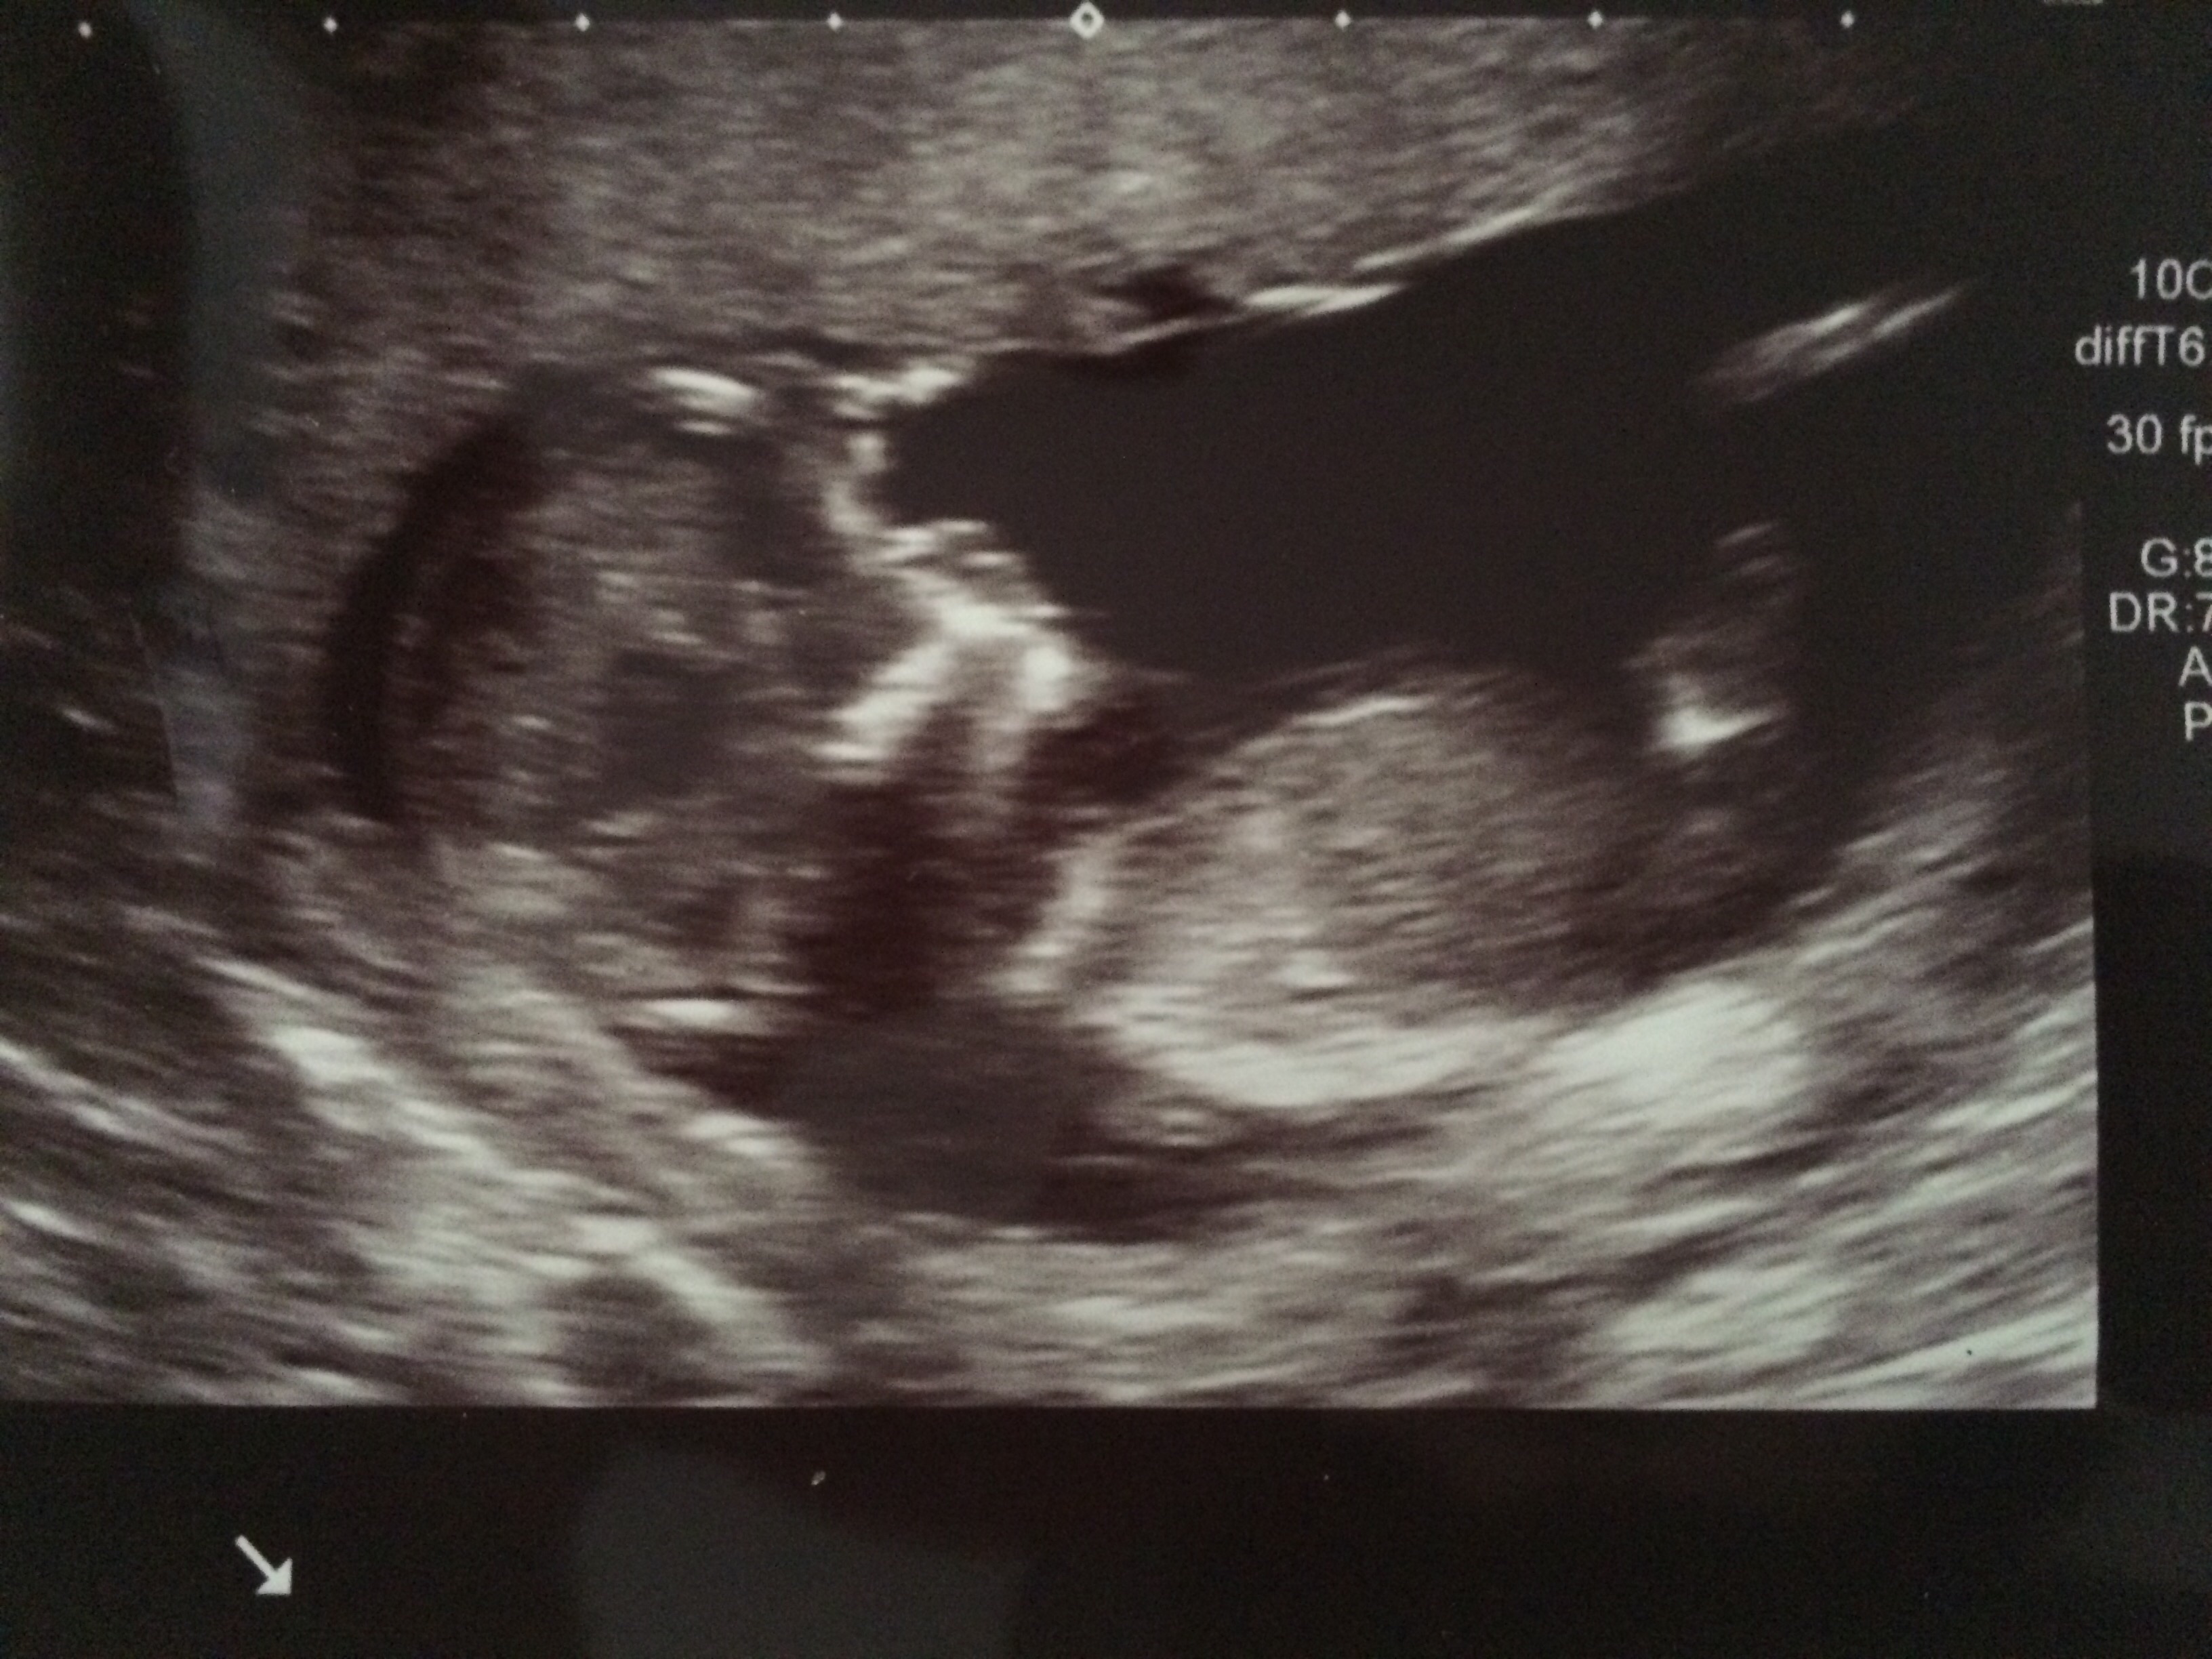

You mentioned that you're 12 weeks along. 19 week gender scan accuracy. My baby boy in 12 week scan | gender prediction week 12 ultrasound. Ultrasound imaging performed in the 11th and 12th weeks of pregnancy for fetal gender identification identified the fetus either as a girl, a boy, or as a the sagittal sign for sonographic prediction of fetal gender in the early second trimester is described and its sensitivity and accuracy evaluated. Learn more about this theory that can predict the gender of your baby this early gender prediction theory focuses on the angle on the nub in comparison to the spine. 3,074 likes · 5 talking about this. How our 12 week ultrasound showed baby's gender! I had my 12 week ultrasound yesterday, and my tech suggested looking up the nub… read post. Early baby gender predictor explained 2019. My mom bawled her eyes out and you can hear. Would love some guesses on what it is :)&nb. Check out our 12 week ultrasound, where we find out the gender of our baby! 12 week ultrasound gender ultrasound gender prediction pregnancy gender reveal pregnancy goals pregnancy photos baby photos 12 week scan how to 'predict' baby's gender from an early ultrasound.

My mom bawled her eyes out and you can hear. 11 week ultrasound gender prediction november 2019 birth. Nub method has very high accuracy when measuring angle of nub compared to spine! Predictions made by sonographers during routine obstetric ultrasound. 12 week ultrasound gender ultrasound gender prediction pregnancy gender reveal pregnancy goals pregnancy photos baby photos 12 week scan how to 'predict' baby's gender from an early ultrasound. A theory that really works, here's how to use your scan to predict your baby's gender. 12 week ultrasound gender prediction mp3 & mp4. 19 week gender scan accuracy. Experts at babygram use the nub theory to thoroughly analyze your ultrasound. 12 weeks 5 days ultrasound/ gender reveal. We do this using the nub method! Ultrasound and gender detection gender is determined by visually inspecting the ultrasound several studies have been conducted to determine the accuracy of gender prediction at different at 12 weeks, 99% of male gender predictions were correct, and 91% of female predictions were. You mentioned that you're 12 weeks along.

My baby boy in 12 week scan | gender prediction week 12 ultrasound. Ramzi and nub theories, nub and skull. Nub method has very high accuracy when measuring angle of nub compared to spine! Ultrasound imaging performed in the 11th and 12th weeks of pregnancy for fetal gender identification identified the fetus either as a girl, a boy, or as a the sagittal sign for sonographic prediction of fetal gender in the early second trimester is described and its sensitivity and accuracy evaluated. You must also remember that a nub analysis before 12 weeks of pregnancy, especially for babygram can give you a reliable prediction of your baby's gender. Ultrasound and gender detection gender is determined by visually inspecting the ultrasound several studies have been conducted to determine the accuracy of gender prediction at different at 12 weeks, 99% of male gender predictions were correct, and 91% of female predictions were. But if baby is only measuring 12 weeks exactly it's still early and there is still time to change. Check out my designer online children's. Experts at babygram use the nub theory to thoroughly analyze your ultrasound. 12 week ultrasound for gender reveal. 12 week ultrasound gender prediction mp3 & mp4. Biomedical papers of the medical faculty of the university palacky, olomouc, czech republic (2012) 5. My mom bawled her eyes out and you can hear.